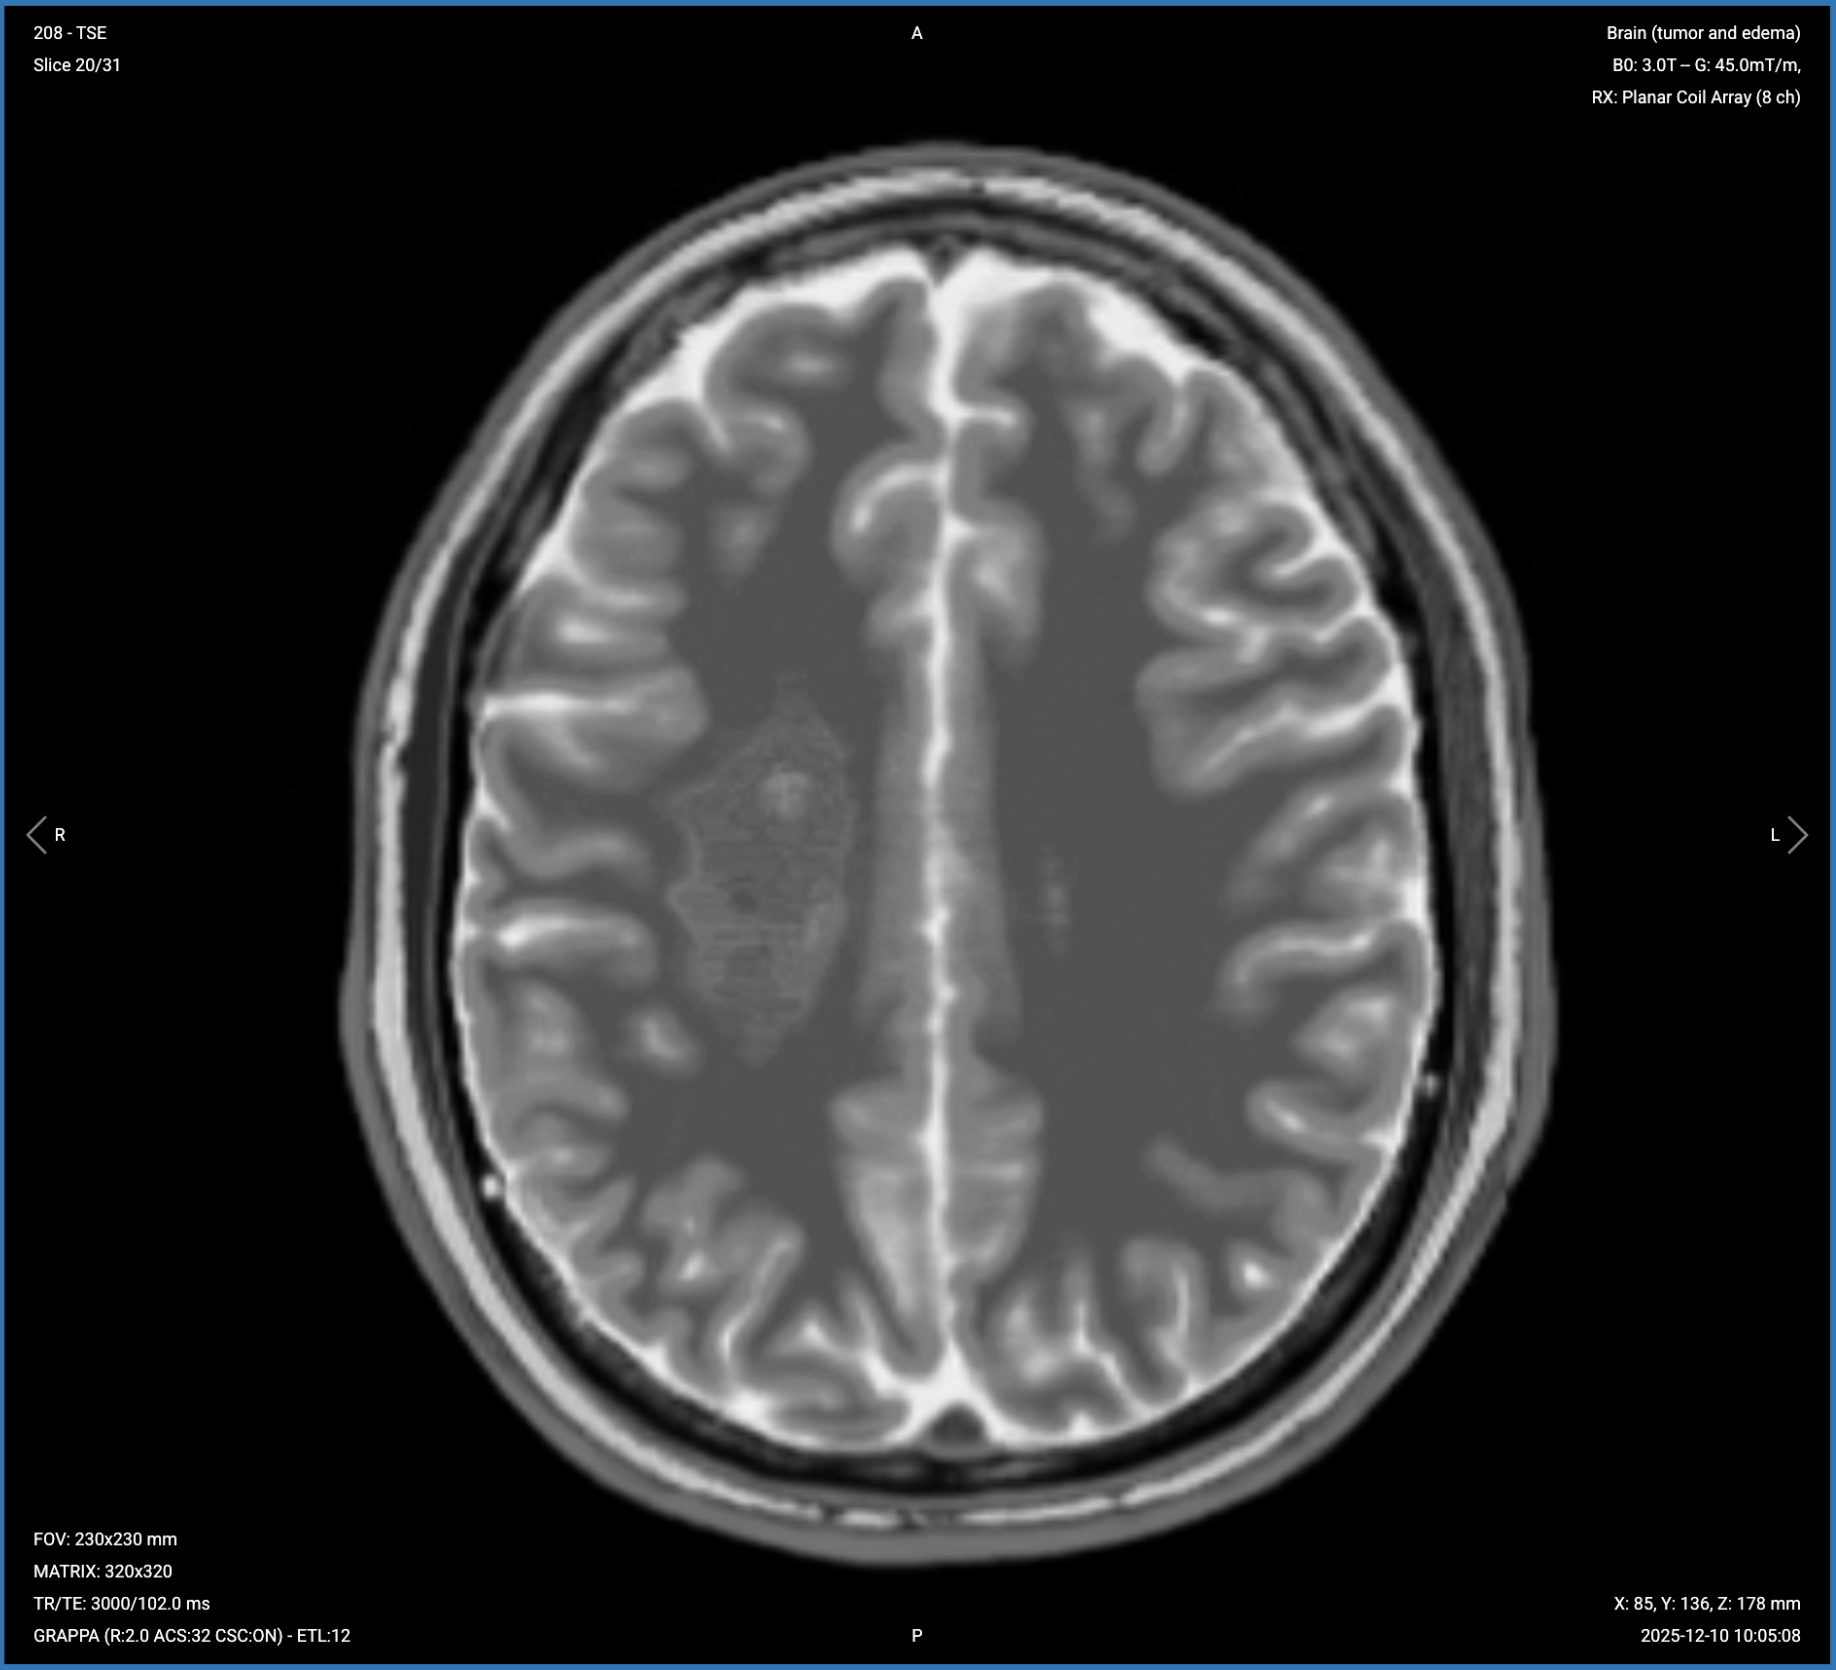

T2 TSE – Shows Tumor Internal Composition and Edema

T2-weighted imaging makes fluids appear bright. This contrast is ideal for tissues and abnormalities with high water content.

In brain tumor imaging, T2 sequences enable us to tell apart cystic and solid components. We can assess the internal architecture and identify edema. For example, a nucleus with liquid hyperintensity on T2 may have a capsule with lower intensity around it. This helps distinguish areas of edema from infiltration and different tumor consistencies.

We acquire this sequence in the axial plane because it provides the best view for assessing left-right symmetry, tumor composition, and mass effect on midline structures and ventricles.

Axial T2 TSE of the Brain – Correct Image Example:

Things to Look for in Axial T2 TSE:

• Tumor composition – cystic areas (bright) versus solid components (lower signal).

• Internal architecture – capsules, multiple compartments, or uniform structure.

• Vasogenic edema surrounding the lesion, appearing bright.

• Mass effect on ventricles, sulci, and midline structures.